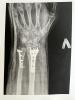

Мне летом руку собирали из кусочков практически, поставили две пластины. Операция под общим наркозом, швы не болели, сама рука болит до сих пор, такие переломы сказали до двух лет срастаются.